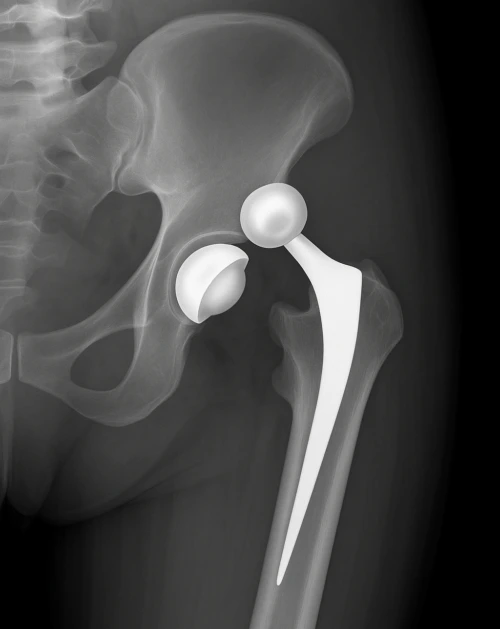

La protesi totale d’anca (Total Hip Arthroplasty, THA) è un intervento chirurgico che sostituisce le superfici articolari malate dell’acetabolo (bacino) e della testa del femore con componenti artificiali. L’obiettivo è ridurre il dolore, ripristinare la funzione e migliorare la qualità di vita.

- Coppa acetabolare (metallo/ceramica, con o senza rivestimento poroso per l’osteointegrazione)

- Inserto (polietilene altamente cross-linkato o ceramica)

- Stelo femorale (metallo, cementato o non cementato)

- Testa femorale (ceramica o metallo)

- Cementata: stelo e/o coppa fissati con cemento acrilico (PMMA). Vantaggi: stabilità immediata, utile in osso osteoporotico. Svantaggi: difficoltà revisione.

- Non cementata: superfici porose o rivestite che favoriscono osteointegrazione. Vantaggi: biologica, revisioni più agevoli. Svantaggi: rischio mobilizzazione iniziale se scarsa stabilità primaria.

- Ibrida: combinazione di cementata/non cementata.